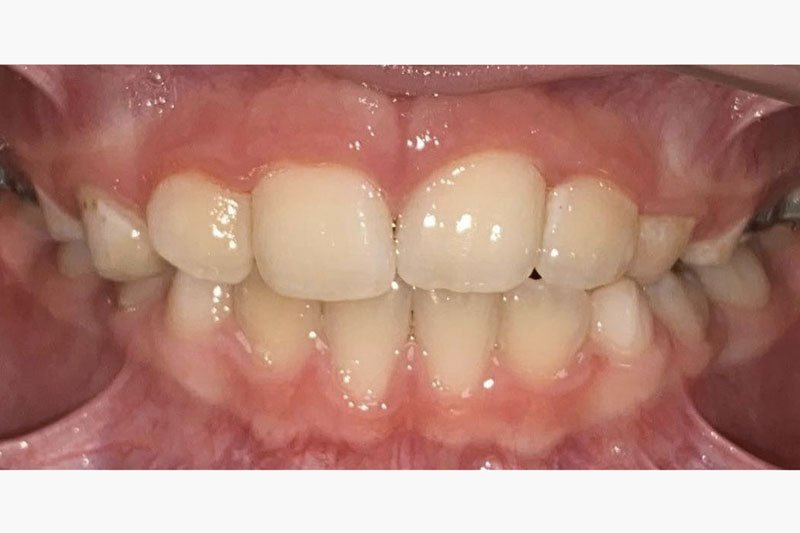

Get the bright white smile you’ve always wanted! Contact us today to get your $139 whitening trays.